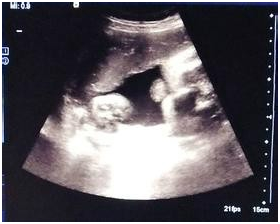

2、B超检查时间:B超检测早孕的时间一般是在月经推迟一周左右可以去医院做B超检查看是否怀孕,如果在B超下能看到妊娠光环就说明怀孕了。